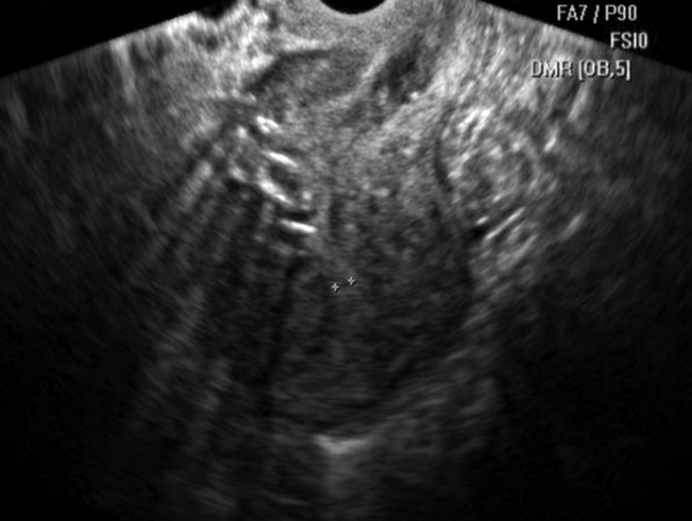

The thickness of the scar formed after metroplasty, as measured by ultrasound on the 6th-7th day after surgery in the group where PRP was applied, averaged 8.4±2.7 mm. Whereas, in the group without PRP, the average scar thickness on days 6-7 was 9.9±1.2, which was 1.6 times higher than in the comparison group. Apparently, the greater scar thickness was associated with delayed scar repair processes due to edema. Examination of the scar after 6 months showed a decrease in scar thickness in both subgroups, with the values falling within statistically non-significant differences compared to the control group (Fig. 2, 3). | Figure 2. Patient U., 27 years old, 6 days after metroplasty |